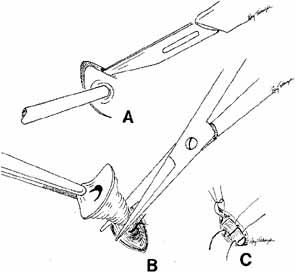

as previously described.  Fig. 55 Closed bypass tube method. This method is used when a dacryocystorhinostomy (DCR) was

completed as an earlier procedure. A 2-mm

trephine is slipped down over a guide needle that is placed at an

appropriate angle running through the previous DCR ostium into the nose. A

portion of the caruncle can be removed to facilitate placement. Fig. 55 Closed bypass tube method. This method is used when a dacryocystorhinostomy (DCR) was

completed as an earlier procedure. A 2-mm

trephine is slipped down over a guide needle that is placed at an

appropriate angle running through the previous DCR ostium into the nose. A

portion of the caruncle can be removed to facilitate placement.